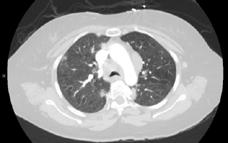

A 58-year-old female with recently diagnosed COVID-19 pneumonia was found to have a dry cough and dyspnoea in the setting of persistent bilateral hilar and mediastinal lymphadenopathy associated with bilateral nodular infiltrates. Of note, she immigrated to the USA from India 10 years prior, with the most recent travel to India 2 years ago. Quantiferon testing upon return to the USA was negative at that time. Workup included bronchoscopy with endobronchial ultrasound revealing non-caseating granulomas with negative stains for acid-fast bacilli (AFB). She was diagnosed with Stage 3 sarcoidosis and initiated on prolonged steroid taper with improvement of symptoms. With taper of steroid dose, however, she developed lymphocyte-predominant exudative effusion with negative cultures, and was reinitiated on a protracted steroid course with rapid symptom resolution. At 4-month follow-up, she had worsening CT findings upon steroid taper, and was started on azathioprine. One month later, she required hospital admission for worsening dyspnoea and fatigue. She was noted to be febrile, tachycardic, and tachypnoeic with worsening

hypoxia. Subsequent CT chest showed progression of bilateral nodular infiltrates with new right upper lobe consolidation and air bronchograms concerning for multifocal pneumonia (Figure 1). Incidentally, she was also noted to have calcified splenic granulomas. She developed rapid clinical deterioration, ultimately requiring mechanical ventilation, pressor support, and continuous renal replacement therapy. Repeat bronchoscopy revealed diffuse alveolar haemorrhage with multiple AFB smears positive for Mycobacterium tuberculosis. She was immediately initiated on quadruple therapy, but unfortunately, despite treatment, developed refractory shock and passed away 2 weeks after initial presentation.

A) Initial adenopathy with peripheral patchy ground glass opacities in the right lung following COVID-19 pneumonia. B) Persistent bulky adenopathy 1 year after initial presentation. C) Extensive nodularity throughout the right lung with increasing confluent opacities in the right upper lobe and stable mediastinal lymphadenopathy 2 years after initial presentation. D) Tuberculosis superimposed on sarcoidosis with progression of nodular infiltrates, worsening right upper lobe consolidation, and air bronchograms with incidental calcified splenic granulomas (not pictured).

Figure 1: CT progression of patient’s sarcoidosis and tuberculosis.